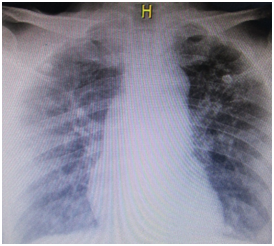

In laboratory studies, hypoxia is reported due to increased lactate plus hypoxemia due to a decrease in partial blood pressure of oxygen, severe acute respiratory distress syndrome, leukocytosis with neutrophilia, elevated C-reactive protein, hyponatremia, hypocalcemia, and urea nitrogen. High creatinine, calculated glomerular filtration rate of 15.6 cckg /min/m2 and a BUN / Cr ratio of 18.4; Hyperbilirubinemia is found at the expense of direct bilirubin, increased transaminase levels, normal coagulation tests, and hyperamylasemia. The chest radiograph shows bilateral opacities of peripheral and parahilar predominance (Figure 2). Respiratory failure is worthy of or tracheal intubation and application of mechanical protective ventilation, intravenous fluid administration continues, intravenous steroid is initiated, enteral N-acetylcysteine, Vitamin E, Vitamin A, Vitamin C, intravenous Colchicine, loop diuretic, thromboprophylaxis and prophylaxis of stress ulcers. He is admitted to the intensive care unit where renal replacement therapy begins.

Figure 2 Chest radiograph of the patient of the described case, that shows bilateral opacities of peripheral and parahilar predominance.

In view of initial oxygen desaturation, low PAFI, PO2 less than 60 mmHg, and the presence of mucosal scoria lesions, we are forced to protect the airway with orotracheal intubation and management with invasive mechanical ventilation; being aware of the collateral damage that would induce oxygen in the generation of free radicals, as previously mentioned. Grosso modo this lung injury will produce an infiltration of fibroblasts, decreasing the ventilation perfusion ratio; which is exacerbated by the destruction of type I and II pneumocytes, and, thereby altering the alveolar surface tension resulting in subsequent pulmonary fibrosis, evident findings on chest radiography and clinical necropsy.

2. The proliferative phase: consists of the development of pulmonary fibrosis as a compensatory repair mechanism against the destruction of alveolar epithelial cells with greater synthesis of fibroblasts and greater secretion of collagen, concluding in the limitation of gas exchange and deformity of the normal alveolar architecture. Our patient was in the proliferative phase due to fibrotic findings both at the radiological level and at the pathological level, which determined the irreversible and unfavorable course.